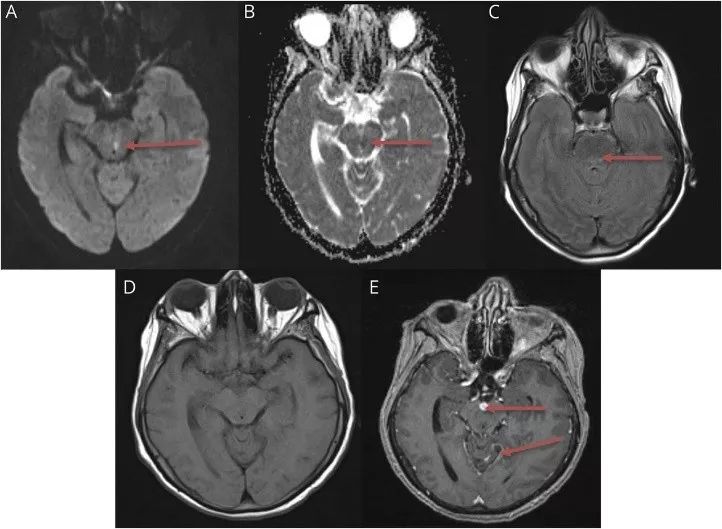

脑部MRI显示脑干和小脑软脑膜多发结节性增强,中脑和脑桥多个急性梗死灶(图1)。颈椎MRI平扫未见脊髓高信号改变。腹部/盆腔MRI平扫和增强显示胰体有4 mm的点状T2高信号。头部CT、头颈部MRA和胸部X线均无异常。

图1 头颅MRI显示软脑膜增强和梗死。 (A)弥散加权成像显示中脑梗死。(B)表观扩散系数显示中脑梗死。(C)Flair显示桥脑梗死。(D)T1平扫和(E)T1增强显示脑干和小脑软脑膜增强。